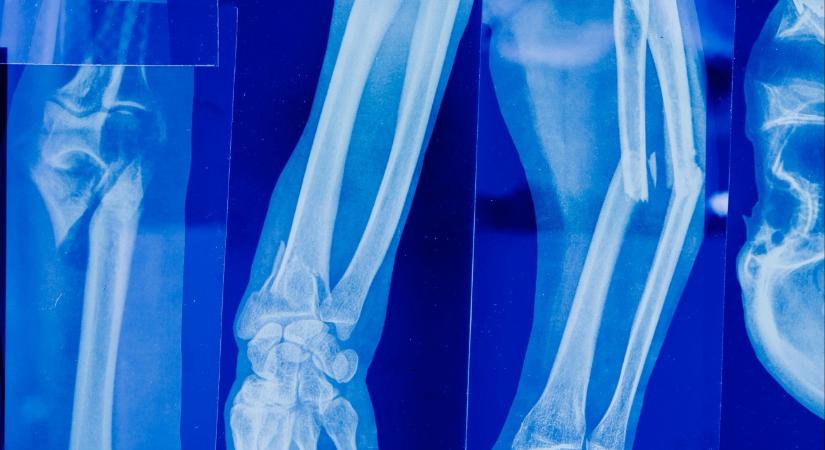

Súlyos baleset történt egy nyíregyházi bölcsődében: egy kétéves kisfiú júliusban az udvaron játszva combcsontját törte. A gyermeket többször meg kellett operálni, és újra kellett tanulnia állni és járni – derült ki az RTL Híradó riportjából.